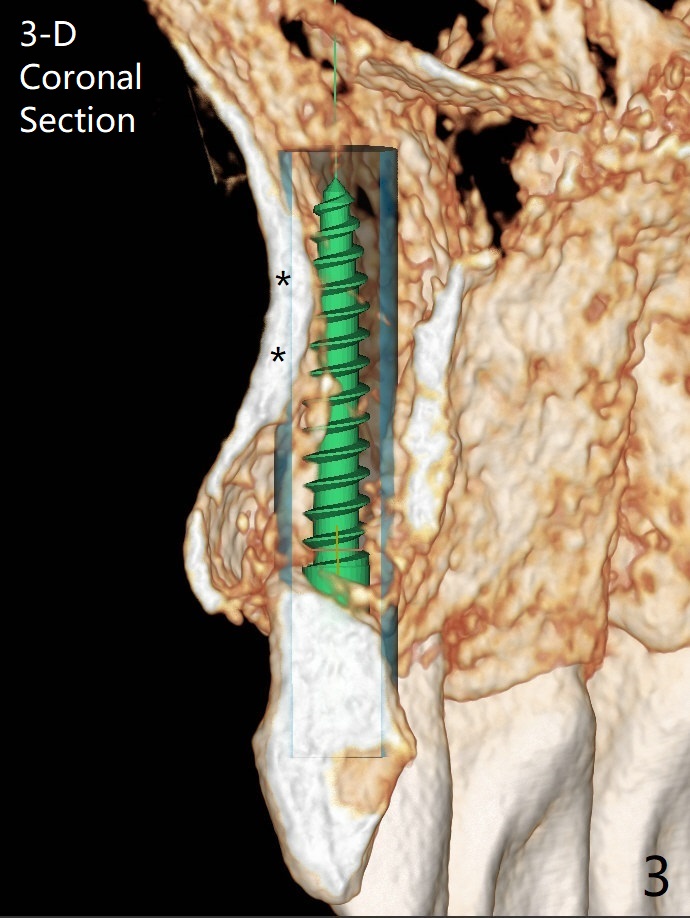

Since there is limited vertical and horizontal (buccopalatal) space at H, it appears that 1-piece implant may offer simple treatment to avoid angled abutment (Fig.1). Because of the thin concave buccal plate over the narrow implant (Fig.2,3,4 *), a remote incision will be made immediately post implantation (Fig.5 red line). After subperiosteal dissection, bone graft will be deposited to avoid implant thread exposure and restore the canine prominence (Fig.6,7). Prepare PRF for sticky bone. Take preop photo to show buccal apical concavity.